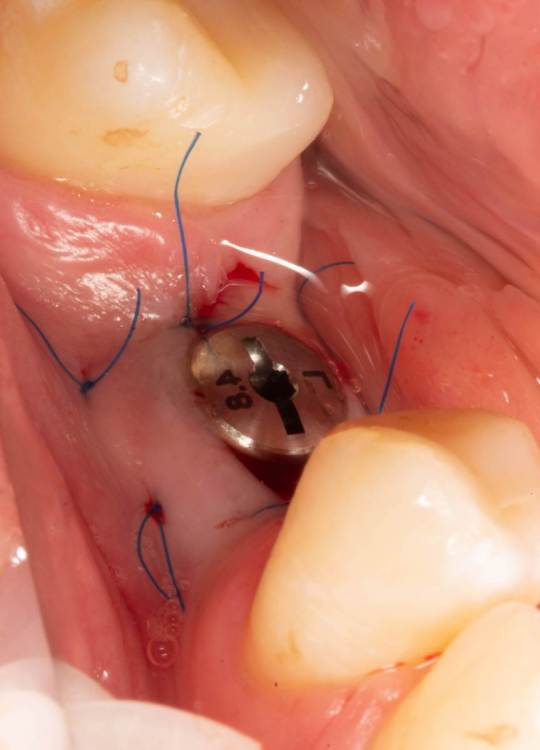

Женька Опубликовано 19 июня, 2023 Поделиться Опубликовано 19 июня, 2023 Здравствуйте, коллеги. Примерно с нового года начал ставить ТЛ имплантаты Дентиум. Что-то под заглушку (не поймал торки, представляете?). Что-то на низких формирвателях. И вот пришла пора протезирования, но отпустить к ортопеду не подготовив десну - не получается. Создал сам себе проблем, сегодня вот исправлял. Получилось неплохо? 3 Ссылка на комментарий

TIGER Опубликовано 20 июня, 2023 Поделиться Опубликовано 20 июня, 2023 Это ж не TL,cубкрестально же.А так я бы длиннее брал ССТ,с захватом соседей Ссылка на комментарий

Женька Опубликовано 20 июня, 2023 Автор Поделиться Опубликовано 20 июня, 2023 @TIGER в смысле это не ТЛ?))) Фото с редукцией не сделал. А то что, шейку погружал - так нужно было. Но это ТЛ. Поверьте) я был на имплантации) Ссылка на комментарий

АнтонТЛТ Опубликовано 20 июня, 2023 Поделиться Опубликовано 20 июня, 2023 Думаю имеется ввиду что имплантат TL установлен по протоколу BL Ссылка на комментарий

Женька Опубликовано 20 июня, 2023 Автор Поделиться Опубликовано 20 июня, 2023 @АнтонТЛТ мы же позиционируем платформу относительно зенита? Есть ли разница тогда, какой имплантат мы выбираем? Вообще весь смысл здесь был заложен в том, что толщина гребня была не очень. Хотелось поставить тонкий имплантат 3.6. Но рисковать тонкой платформой не хотелось, поэтому выбор пал на 4.8 платформу ТЛ и тело имплантата 3.6 1 Ссылка на комментарий